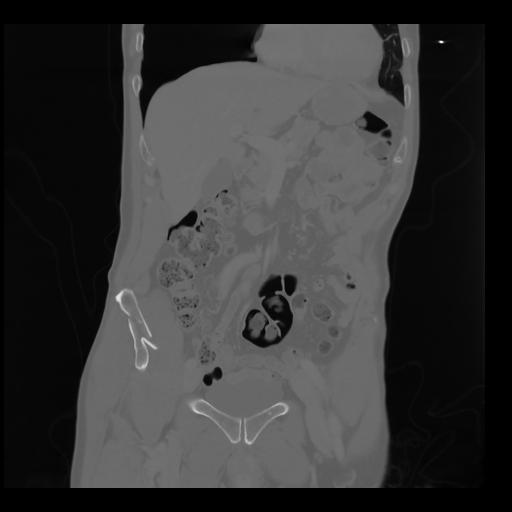

35 CUERPO,CE,Coronal,3.000,CUERPO,Coronal,